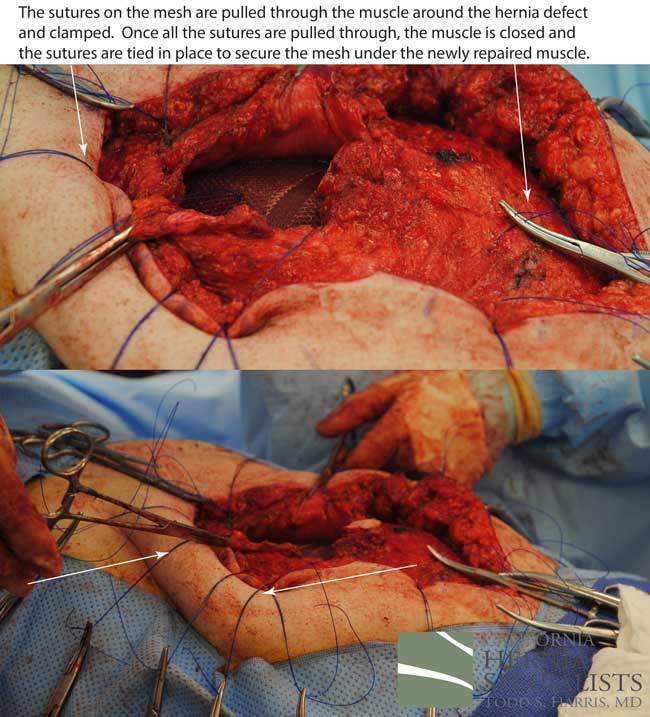

The more complete approach would be to bring healthy muscle together at the mid line. Only after the muscle is repaired completely, can a mesh be used to SUPPORT the muscle repair. Meshes should not be considered a bridge from healthy muscle to healthy muscle. Instead mesh should be used as a reinforcement of a correct hernia repair.

This technique requires more surgical time, recovery time, and usually several days in the hospital. However, this patient chose to proceed with the open hernia repair. Below are some of the pictures from his surgery as well as post operative CT scan image and photos of the patient.

Because this patient had failed two prior surgeries, we performed a complex open hernia repair on him. This repair included a technique called ‘component separation’, where the oblique muscles on the sides of the abdomen, are partially released, or cut, to allow the rectus muscles to be pulled back together in the middle of the abdomen.

Since the abdominal muscles were weakened, we placed a sheet of biologic mesh under the muscle in the middle at the area of the hernia hole, closed the muscle over this mesh, then placed another mesh on top of the muscles which were closed. This provided him with three layers of repair.